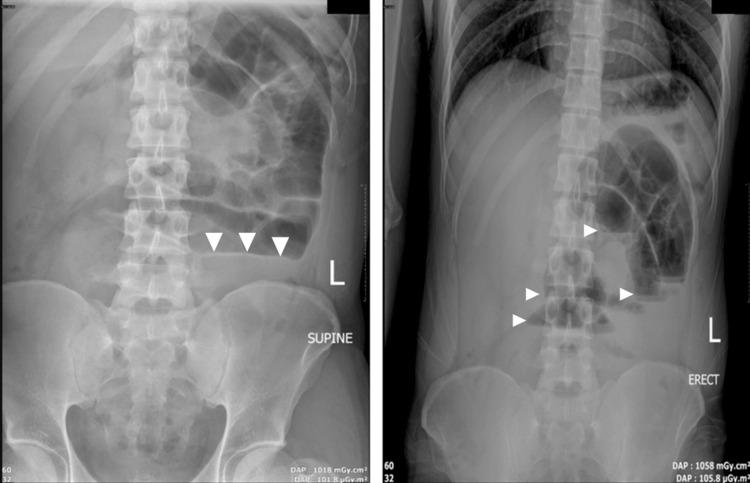

Internal hernias are a rare cause of intestinal obstruction, accounting for a small proportion of cases. Among these, paraduodenal hernias represent a significant subtype and require prompt recognition and intervention to prevent life-threatening complications. We report the case of a 31-year-old male with no significant medical or surgical history who presented with a three-day history of generalized abdominal pain, vomiting, and constipation. Clinical examination revealed abdominal distension, tenderness, and hyperactive bowel sounds. Laboratory findings were unremarkable except for leukocytosis. Abdominal X-ray demonstrated features of small bowel obstruction, and CT imaging identified findings suggestive of a left paraduodenal hernia. Exploratory laparotomy revealed a large encapsulated peritoneal sac originating from the left paraduodenal region and extending into the pelvis. Dilated and edematous but viable small bowel loops were released, and adhesiolysis was performed. A planned second-look surgery two days later confirmed resolution of bowel edema, and the abdomen was closed without complications. Paraduodenal hernias arise from a congenital anomaly involving the mesentery and often present as intermittent or acute bowel obstruction. Diagnosis is challenging due to nonspecific symptoms but can be facilitated by CT imaging. Definitive management involves surgical reduction and repair of the hernia, whether through open or laparoscopic approaches. This case highlights the importance of considering internal hernias in young patients with small bowel obstruction and no prior abdominal surgery. Prompt imaging, timely surgery, and individualized management are crucial for optimal outcomes.

内疝是肠梗阻的罕见病因,占病例的比例较小。其中,十二指肠旁疝是一种重要的亚型,需要及时识别和干预以预防危及生命的并发症。我们报告一例31岁男性患者,无重大内科或外科病史,出现腹痛、呕吐和便秘3天。临床检查发现腹胀、压痛和肠鸣音亢进。实验室检查除白细胞增多外无异常。腹部X线显示小肠梗阻特征,CT成像发现提示左十二指肠旁疝的表现。剖腹探查发现一个大的包裹性腹膜囊,起源于左十二指肠旁区域并延伸至盆腔。松解扩张、水肿但仍存活的小肠袢,并进行粘连松解术。两天后计划进行的二次探查手术证实肠水肿已消退,腹部闭合无并发症。十二指肠旁疝由涉及肠系膜的先天性异常引起,常表现为间歇性或急性肠梗阻。由于症状不具特异性,诊断具有挑战性,但CT成像有助于诊断。明确的治疗包括通过开放或腹腔镜手术对疝进行复位和修补。该病例强调了在无既往腹部手术史的小肠梗阻年轻患者中考虑内疝的重要性。及时的影像学检查、适时的手术和个体化管理对于取得最佳治疗效果至关重要。